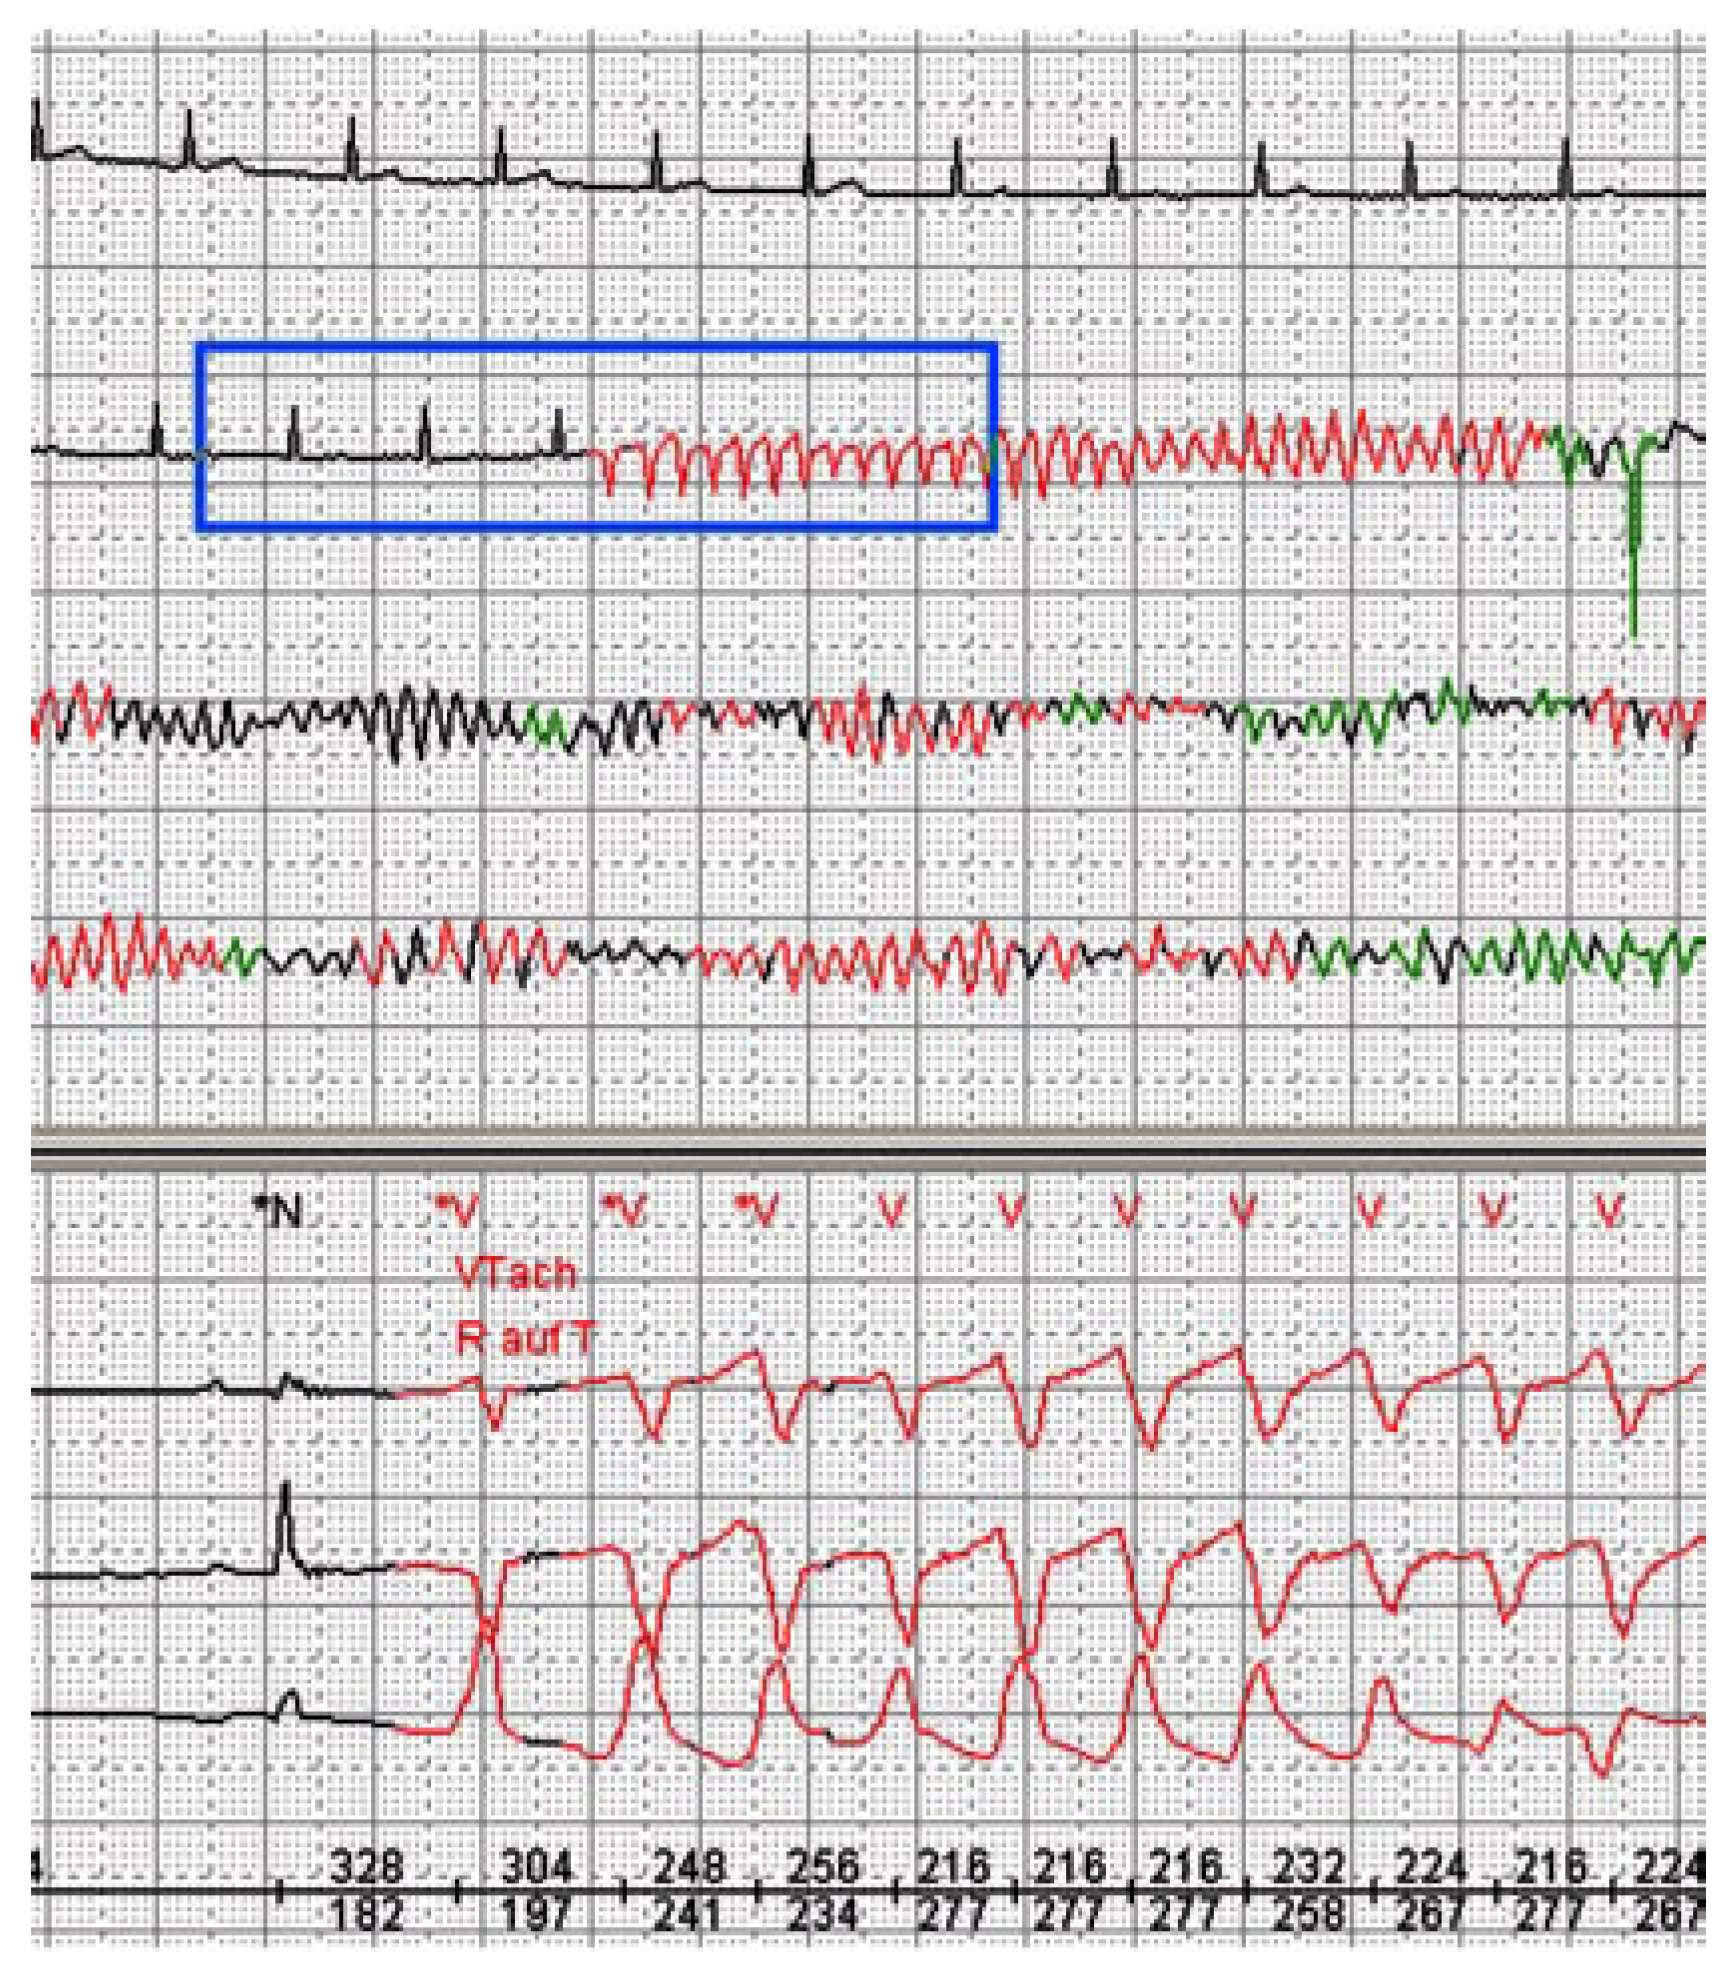

Mechanism of Sudden Cardiac Death in Coronary Artery Disease

Case report